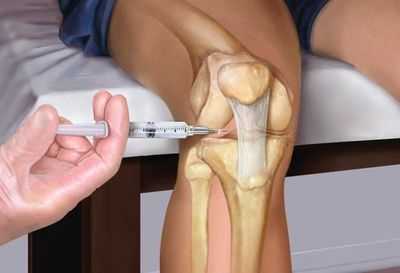

Особенности применения

Для эффективности применения внутрисуставных инъекций вводить их должен исключительно опытный специалист ортопед. В таком случае процедура лечения будет безболезненной и не нанесет вред пациенту. Для проведения манипуляции задействуется шприц с удлиненной иглой, которая направляется непосредственно в область суставной щели. Чтобы минимизировать ошибки в процессе внутрисуставной инъекции применяют регулярный УЗИ-контроль.

Внутрисуставная инъекция в коленный сустав

Внутрисуставные инъекции внутрь суставной ткани колена выполняют при травме, которая сопровождается болезненными ощущениями. Обычно введение лекарства проводится периартикулярным способом либо именно в суставную полость. В зависимости от того насколько тяжело протекает заболевание, укол выполняют на наружной или внутренней стороне.